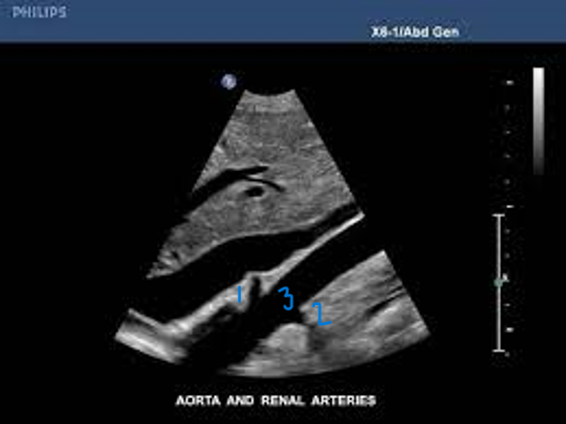

<p>In this Sagittal-Coronal plane, what is #1?</p>

In this Sagittal-Coronal plane, what is #1?

Right Renal Artery

<p>In this Sagittal-Coronal plane, what is #2?</p>

In this Sagittal-Coronal plane, what is #2?

Left Renal Artery

<p>In this Sagittal-Coronal plane, what is #3?</p>

In this Sagittal-Coronal plane, what is #3?

Aorta

<p>What number is known as the RRA</p>

What number is known as the RRA

#3

<p>What is this structure?</p>

What is this structure?

The right and left renal arteries